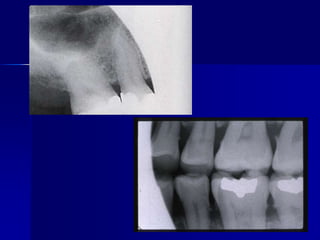

Technique & Projection errorsb. Film placmentartifactApices cut offOccur when the film is not positioned apically enough to record the entire tooth.

Technique & Projection errorsb. Film placmentartifactDropped film cornerThe film edge is not placed parallel to the occlusal surface of the teeth.

Technique & Projection errorsb. Film placmentartifactBlack lineDue to excessive bending of the film prior to its placement inside the patient’s mouth (pressure causes ionization of silver halide upon processing will be darker).

Technique & Projection errorsb. Film placmentartifactnormaldistortionDistortionDue to bending of the film to eliminate the patient’s  discomfort specially in lower premolar area and upper central incisors.

Technique & Projectionerrorsb. Film placmentartifactApices cut offOccur when the film is not positioned apically enough to record the entire tooth.

Technique & Projectionerrorsb. Film placmentartifactDropped film cornerThe film edge is not placed parallel to the occlusal surface of the teeth.

Technique & Projectionerrorsb. Film placmentartifactBlack lineDue to excessive bending of the film prior to its placement inside the patient’s mouth (pressure causes ionization of silver halide upon processing will be darker).

Technique & Projectionerrorsb. Film placmentartifactnormaldistortionDistortionDue to bending of the film to eliminate the patient’s discomfort specially in lower premolar area and upper central incisors.